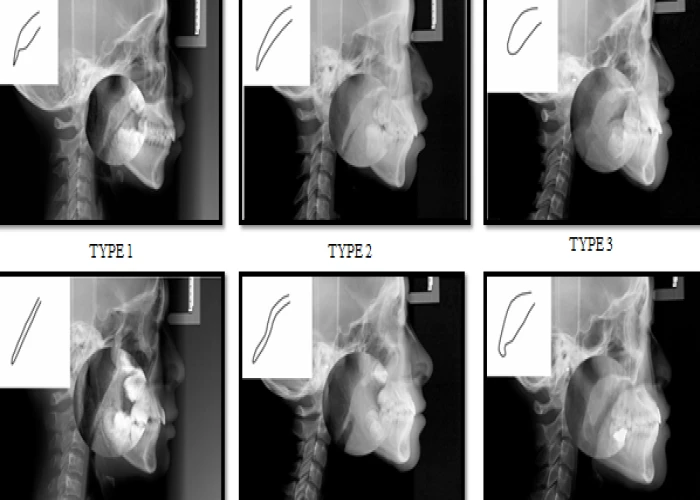

Oral Medicine & Radiology is concerned with diagnosis and medical management of diseases specific to the oral & maxillofacial structures, management of oral manifestations of systemic diseases, management of behavioral disorders, and dental treatment of medically compromised patients. It deals with the diagnostic intraoral and extraoral imaging of maxillofacial structures by both conventional and digital methods. It further includes Forensic Odontology and also promotes tobacco cessation.

Oral Radiologists deals with the diagnostic intraoral and extraoral imaging of maxillofacial structures which includes both conventional and digital imaging where as a General Radiologists deals with the imaging of the rest of the body with the same modalities.